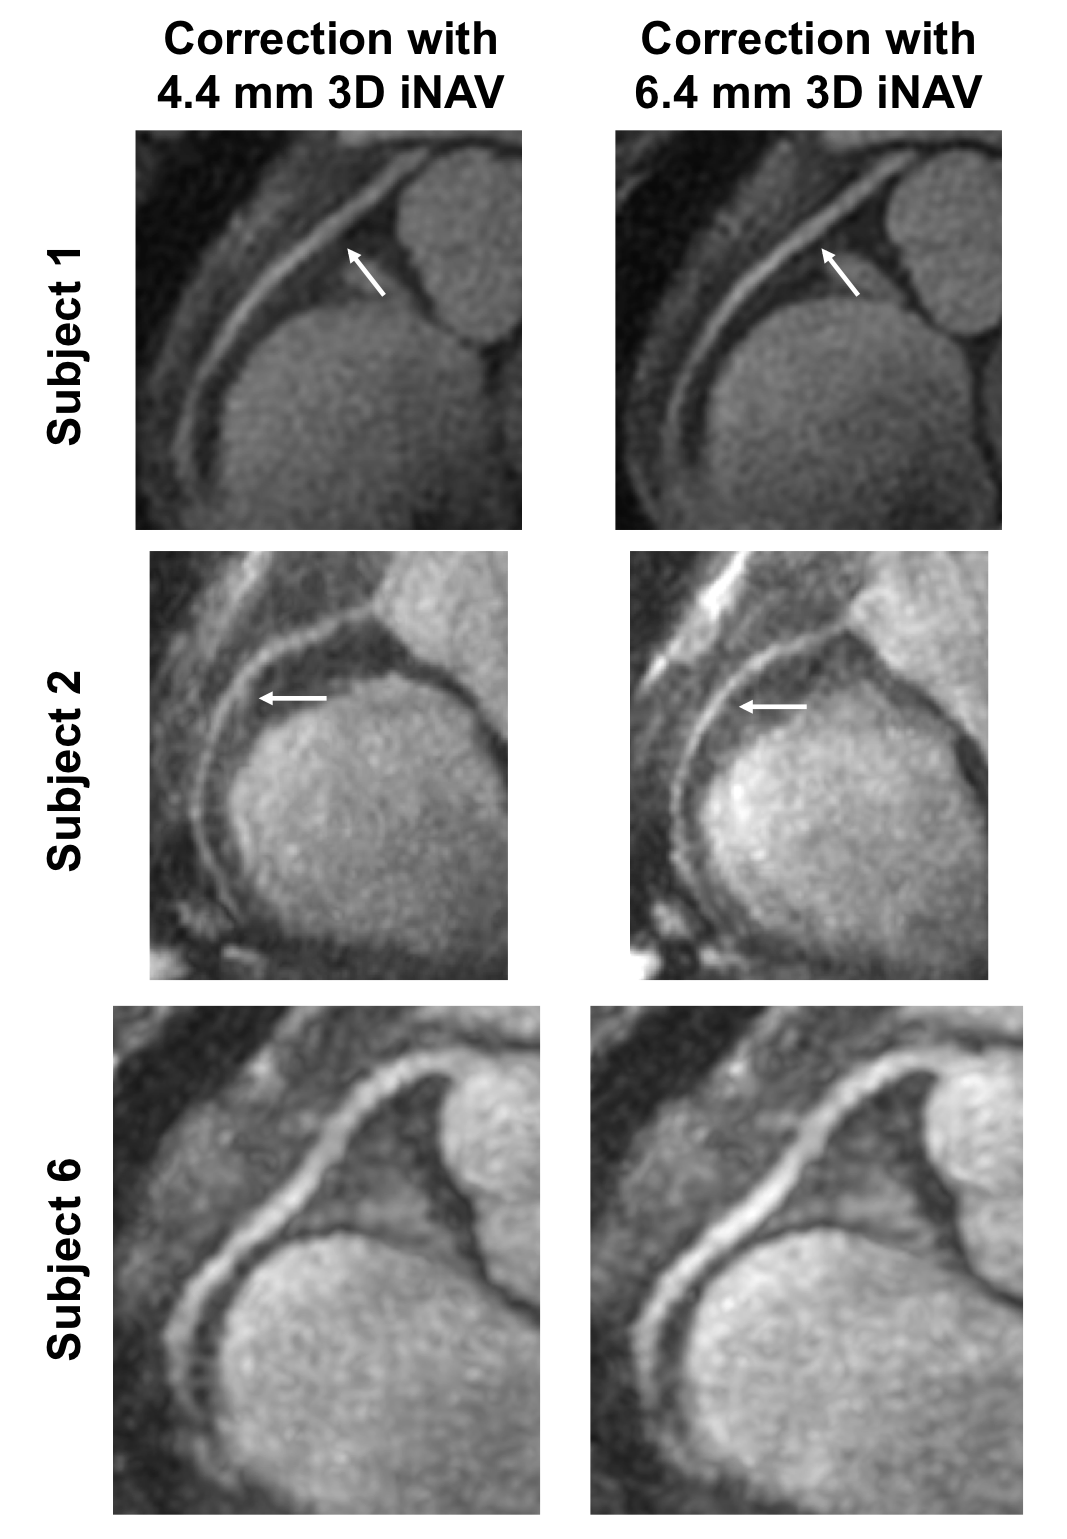

Figure 4: Reformatted MIP of the RCA with autofocusing motion correction using the 4.4 mm 3D iNAV (left) and 6.4 mm 3D iNAV (right) for three subject studies. In Subject 1 and Subject 2, applying the motion information from the 6.4 mm 3D iNAV better delineates the RCA compared to utilizing the 4.4 mm 3D iNAV. Subject 6 is a case where the depiction of the different RCA segments is similar between the two approaches. White arrows indicate regions of notable differences between autofocusing using the 4.4 mm 3D iNAV and 6.4 mm 3D iNAV.

Reformatted oblique thin-slab MIP images depicting the RCA for three volunteer studies are shown in Figure 4. For Subject 1 and Subject 2, autofocusing correction with the 6.4 mm 3D iNAVs results in enhanced depiction of the medial RCA segment compared to correction with the 4.4 mm 3D iNAVs. In the case of Subject 6, the RCA exhibits equivalent sharpness regardless of the applied 3D iNAVs. Similar trends are observed for the LCA in Figure 5. While the medial segment of the LCA is better visualized when using the 6.4 mm 3D iNAVs in place of the 4.4 mm 3D iNAVs for Subject 1 and Subject 2, a difference in sharpness is not observed in the LCA of Subject 6.